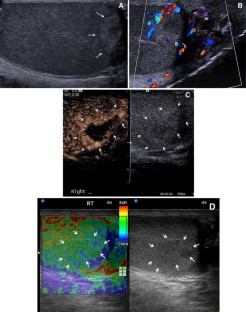

Fig. 3